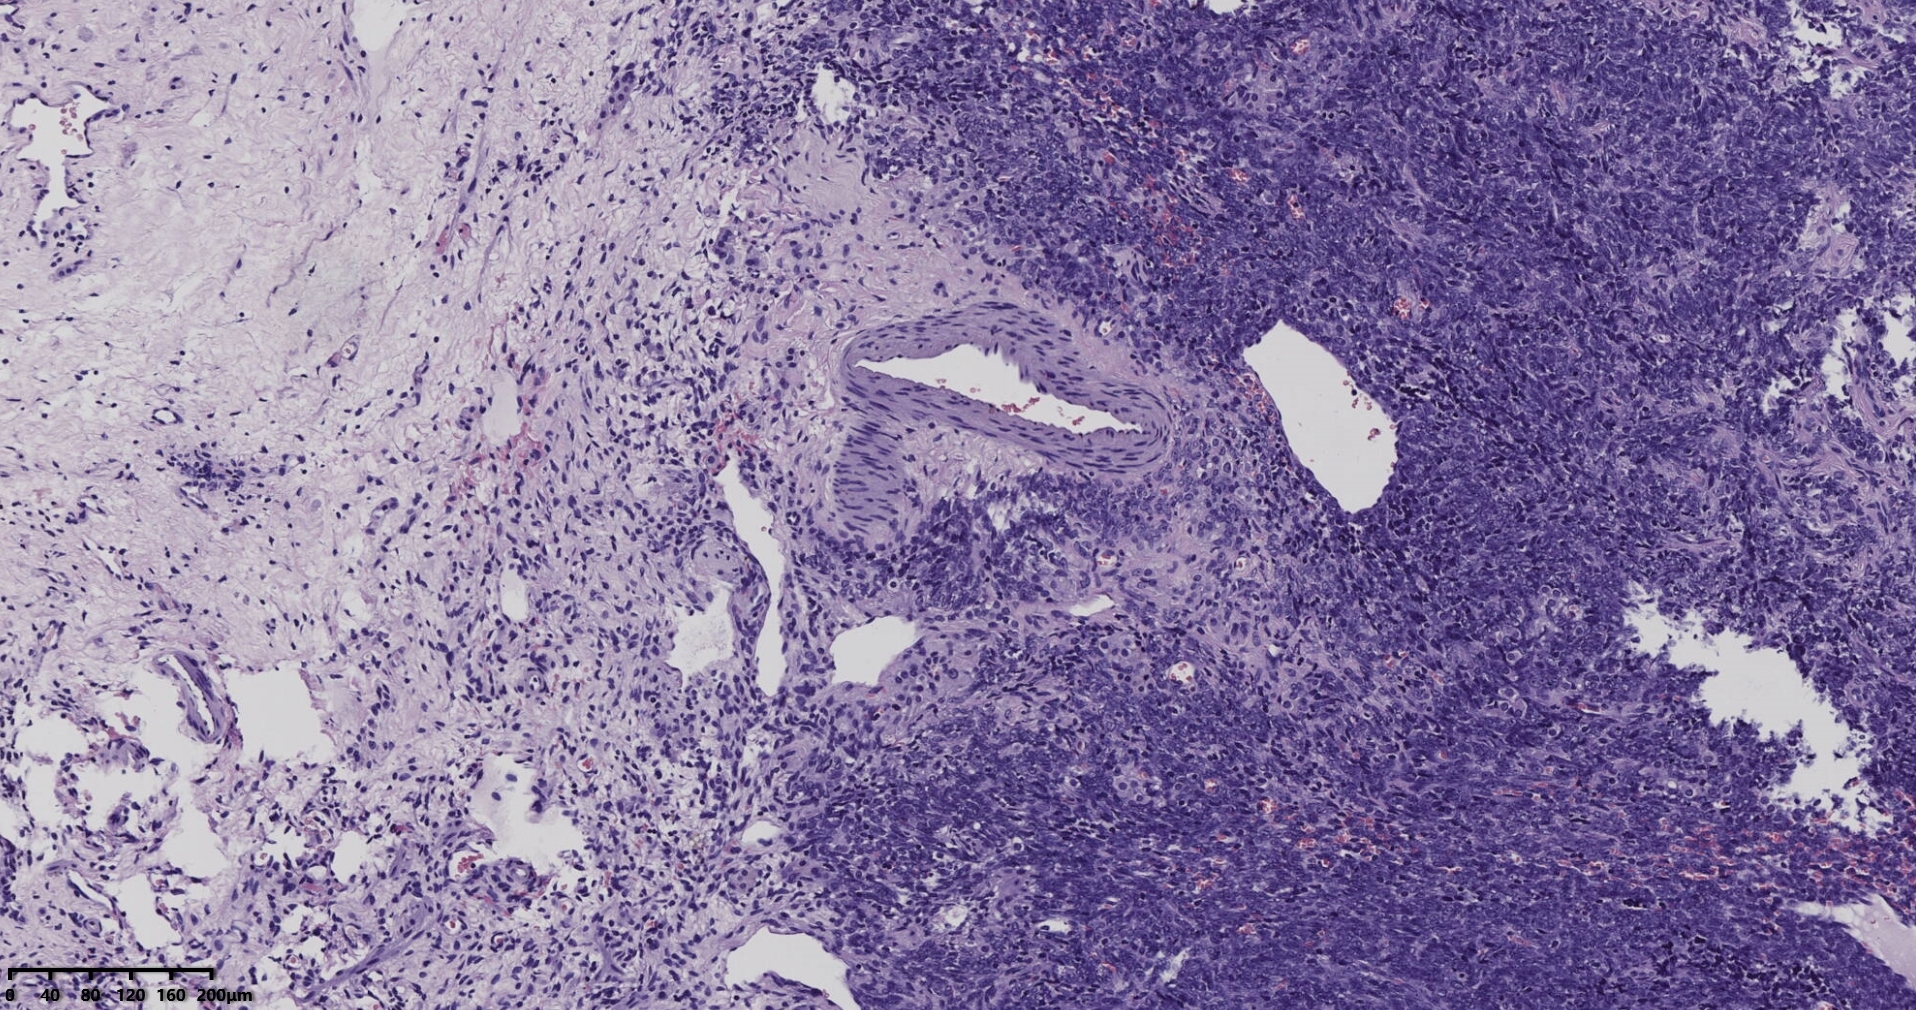

冰冻切片取两块实性区组织,其中1块可见梭形细胞为主,另一块似上皮样细胞,细胞丰富密集。

术中考虑卵巢性索间质来源肿瘤,待石蜡及免疫组化。

常规切片

考虑颗粒细胞瘤。